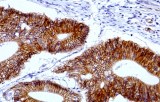

Primary antibodies for immunohistochemistry (IHC) with CE/IVD marking are essential reagents in diagnostic and research pathology, enabling the specific detection of target antigens in formalin-fixed paraffin-embedded (FFPE) tissue sections.

IHC using CE/IVD primary antibodies is a cornerstone in the characterization of gastrointestinal tumors. These antibodies assist pathologists in distinguishing epithelial from mesenchymal origins, determining tumor subtypes, and identifying primary sites in metastatic disease.

- In colorectal cancer, antibodies against cytokeratins (CK7, CK20) and transcription factors such as CDX2 facilitate accurate tumor classification and subtype differentiation.

- In gastric and esophageal adenocarcinomas, IHC highlights metaplastic and dysplastic changes, supporting early detection and prognostic evaluation.

- In gastrointestinal stromal tumors (GISTs), KIT (CD117) expression is reliably detected by IHC, while PDGFRA mutations are evaluated through molecular testing, aiding in targeted therapy decisions.